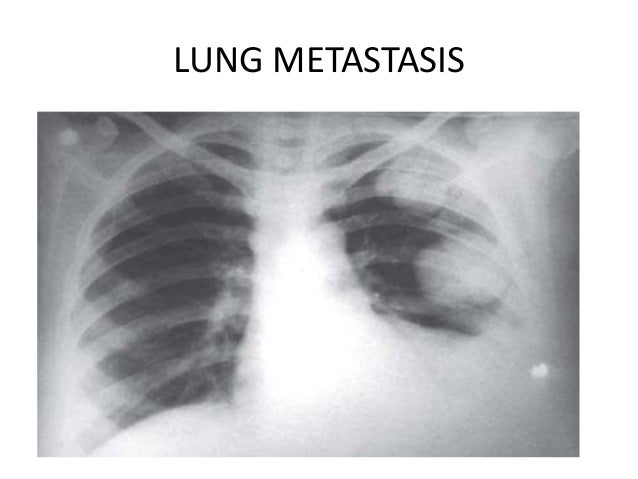

Can Molar Pregnancy Lead To Cancer | You Getting Pregnant

Can Molar Pregnancy Lead To Cancer | You Getting Pregnant www.yougettingpregnant.com